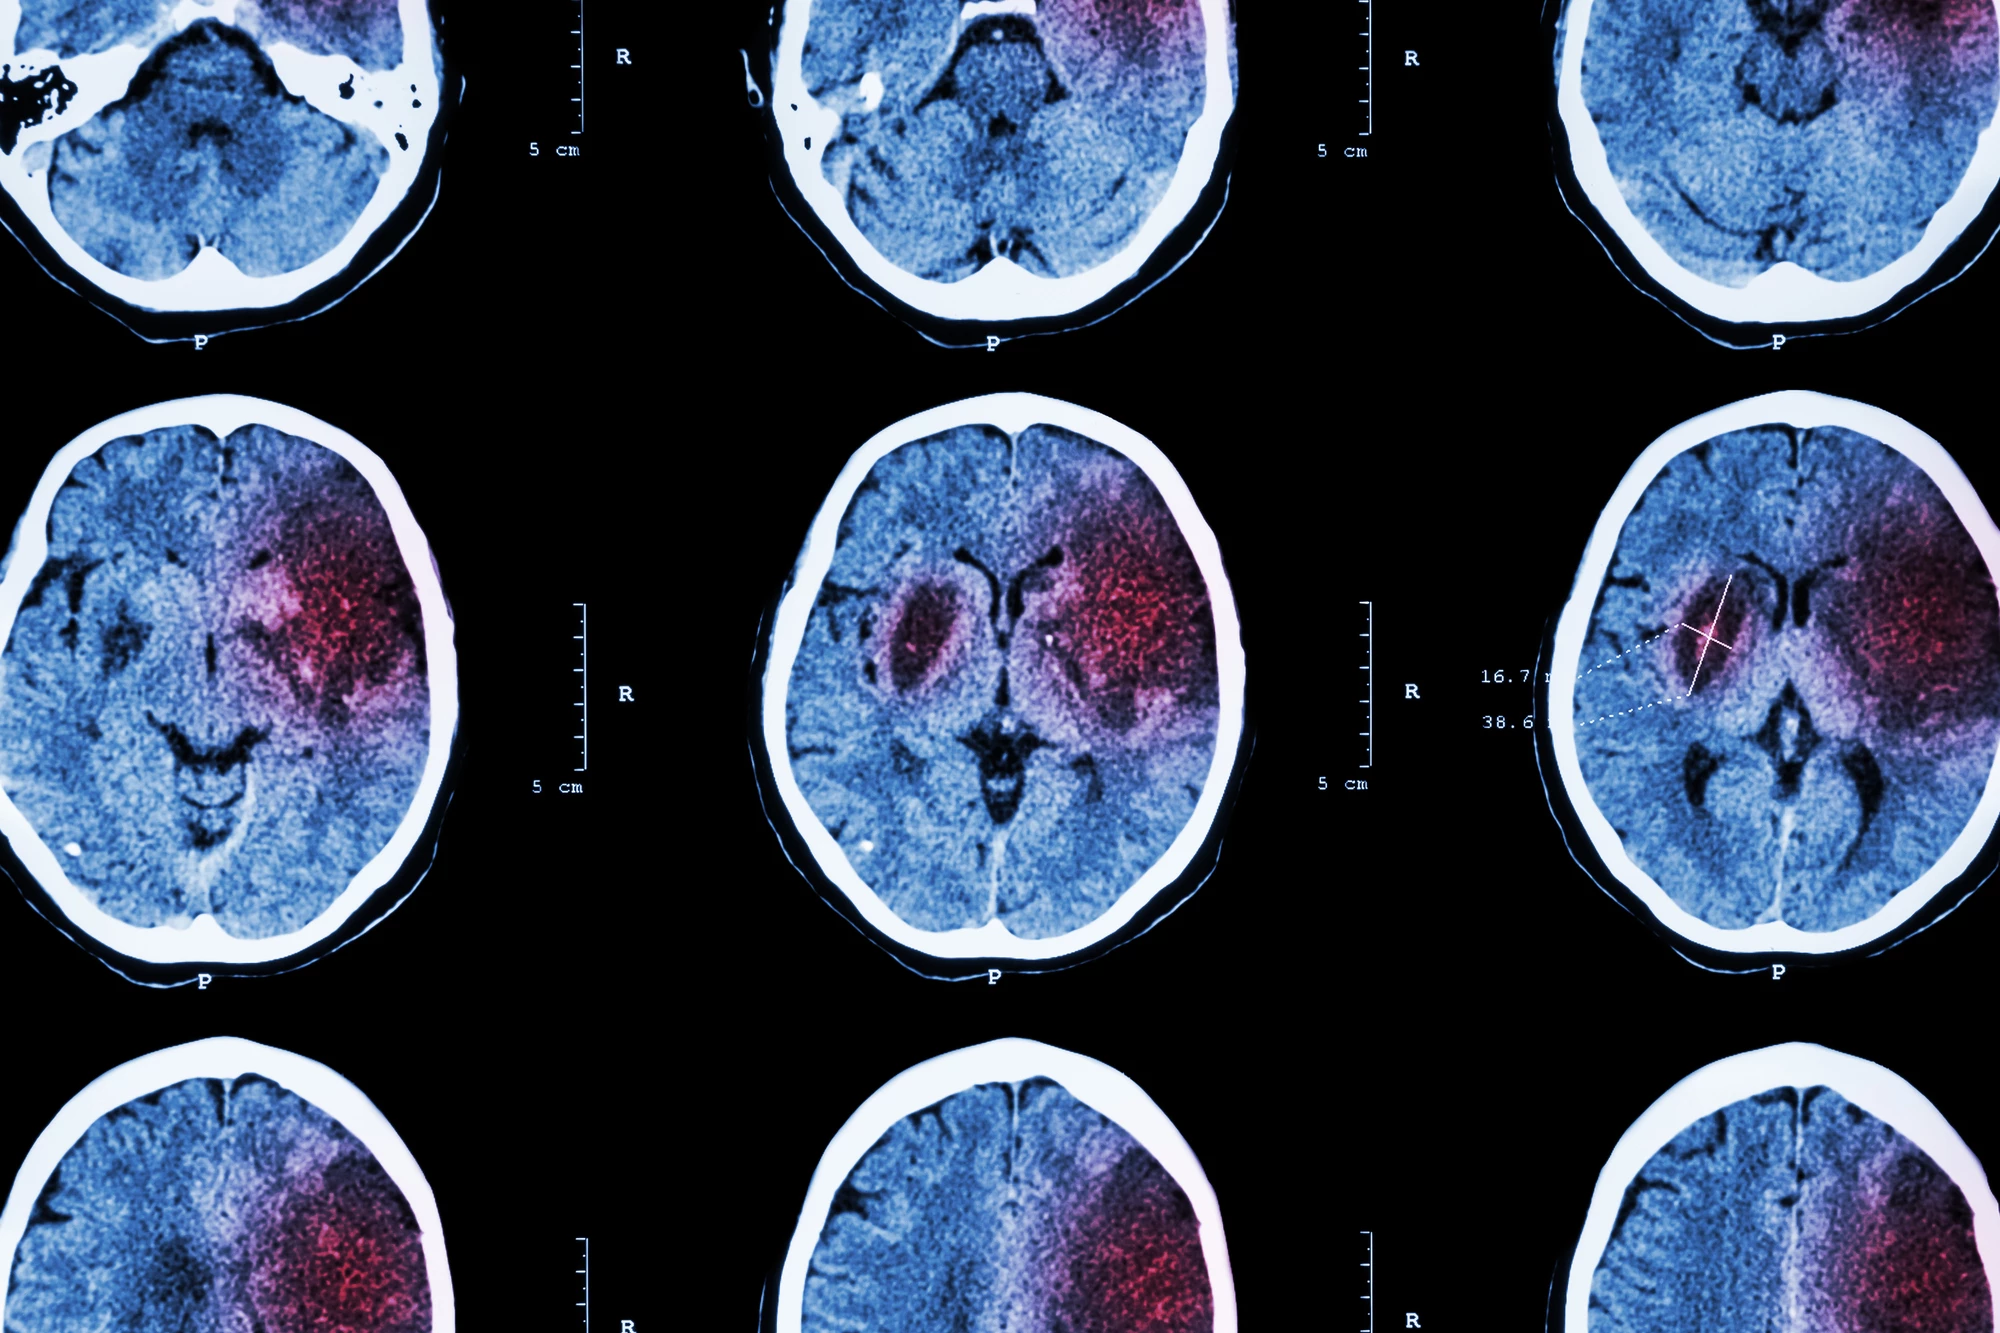

When a blood clot or the build-up of fatty plaques blocks an artery leading to the brain, it cuts off the blood and oxygen supply to an area, causing damage to or death of brain cells. This is known as an ischemic stroke and is the most common type of stroke.